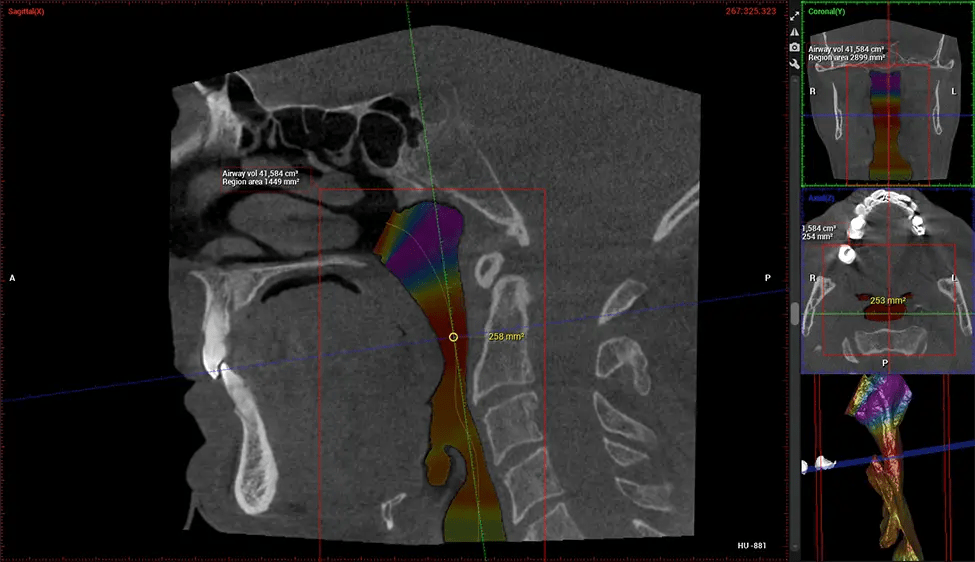

This 3D scan, called cone beam computed tomography, gives your dentist a more complete image of your oral anatomy and disease processes than a traditional X-ray. Unlike conventional X-rays, which capture a 2D image of your mouth from various angles, a 3D scan takes multiple digital X-rays for one image. It provides a complete view of your jaw, teeth, nerves, and soft tissues. This enhanced view allows dentists to detect minor issues not visible in traditional 2D scans, such as impacted wisdom teeth or bone fractures in the sinus cavity.

There are many benefits to using CBCT technology, especially compared to the traditional 2D X-ray format. One of the most significant advantages of CBCT scans is that they provide much more information than traditional X-rays. A scan lets your dentist see images from all angles of your jaw and mouth, including your sinuses, nasal cavity, cheekbones, and other surrounding areas. This added information helps your dentist craft a comprehensive treatment plan that addresses all aspects of your oral health.

After the scanning process, the captured X-ray images are processed by the CBCT software, which applies algorithms to reconstruct a detailed 3D image of the scanned area. The software compiles these individual X-ray images and creates a digital 3D representation of the patient’s anatomy. The reconstructed 3D CBCT image can be viewed and analyzed by the dentist or radiologist. This image can be manipulated, rotated, and zoomed in or out to examine specific structures and evaluate the patient’s condition.